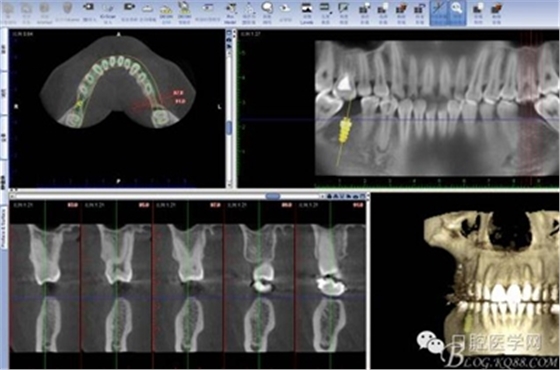

CT

2:16 44根管治療后冠修復(fù),拔除18 28 38 48 后 36 46種植修復(fù) 37 47 遠(yuǎn)中打種植支抗釘扶正37 47 后 種植修復(fù)冠

因?yàn)榛颊咭蟀朐聝?nèi)完成,所以同期植入韓國豋騰4.5*10mm種植體